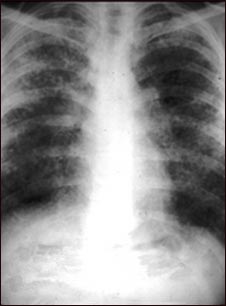

Sarcoidosis, estado II - radiografía de tórax

La sarcoidosis causa daños en el tejido pulmonar que pueden sanar con la cicatrización. Esta diapositiva muestra el área pulmonar, normalmente de apariencia oscura, con un aspecto lechoso y granuloso. Este individuo sufre una grave disminución de la función pulmonar.